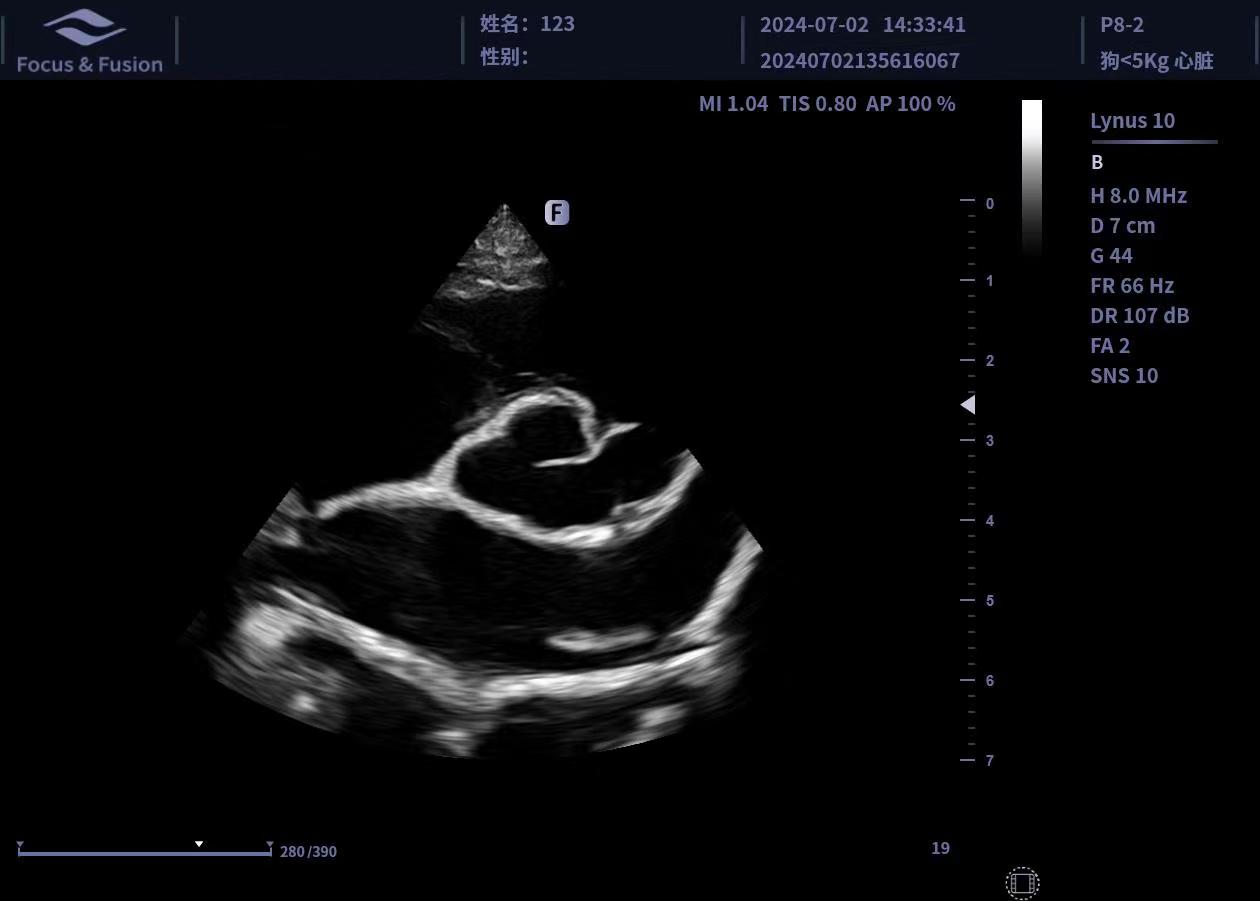

圖片展示

Image List